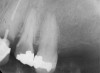

The clinician also must consider the status of the adjacent teeth. Figure 6 shows teeth Nos. 29 and 31 prepared for a fixed bridge. Factors to be considered in this example were the short root of tooth No. 29 with a distal biologic width violation and a short root trunk on tooth No. 31 (which leads to furcation involvement with a small amount of facial or lingual bone loss). This patient also had periodontal disease, which further decreased the long-term prognosis of the fixed bridge option. No prospective studies directly compare the longevity of the two options: a three-unit fixed bridge vs an implant.37 Other factors that complicate comparisons of an implant vs a fixed three-unit bridge are the variability of fixed bridges as well as the variability of the implants (amount of bone, implant length, etc). For example, endodontically treated abutment teeth do not last as long as nonendodontically treated abutment teeth.38 Restorations on teeth with endodontic posts and a minimal length of ferrule do not persist as long as those on teeth without a post and at least a 2-mm ferrule.39

Figure 6   Tooth No. 29 with the temporary build-up close to the osseous crest. Tooth No. 29 has a short post, and tooth No. 31 has a very short root trunk.

Figure 6

Figure 7  Condition of the teeth seen in Figure 6, approximately 5 years after restoration. Note the extensive furcation involvement of tooth No. 31 and its residual periapical radiolucency.